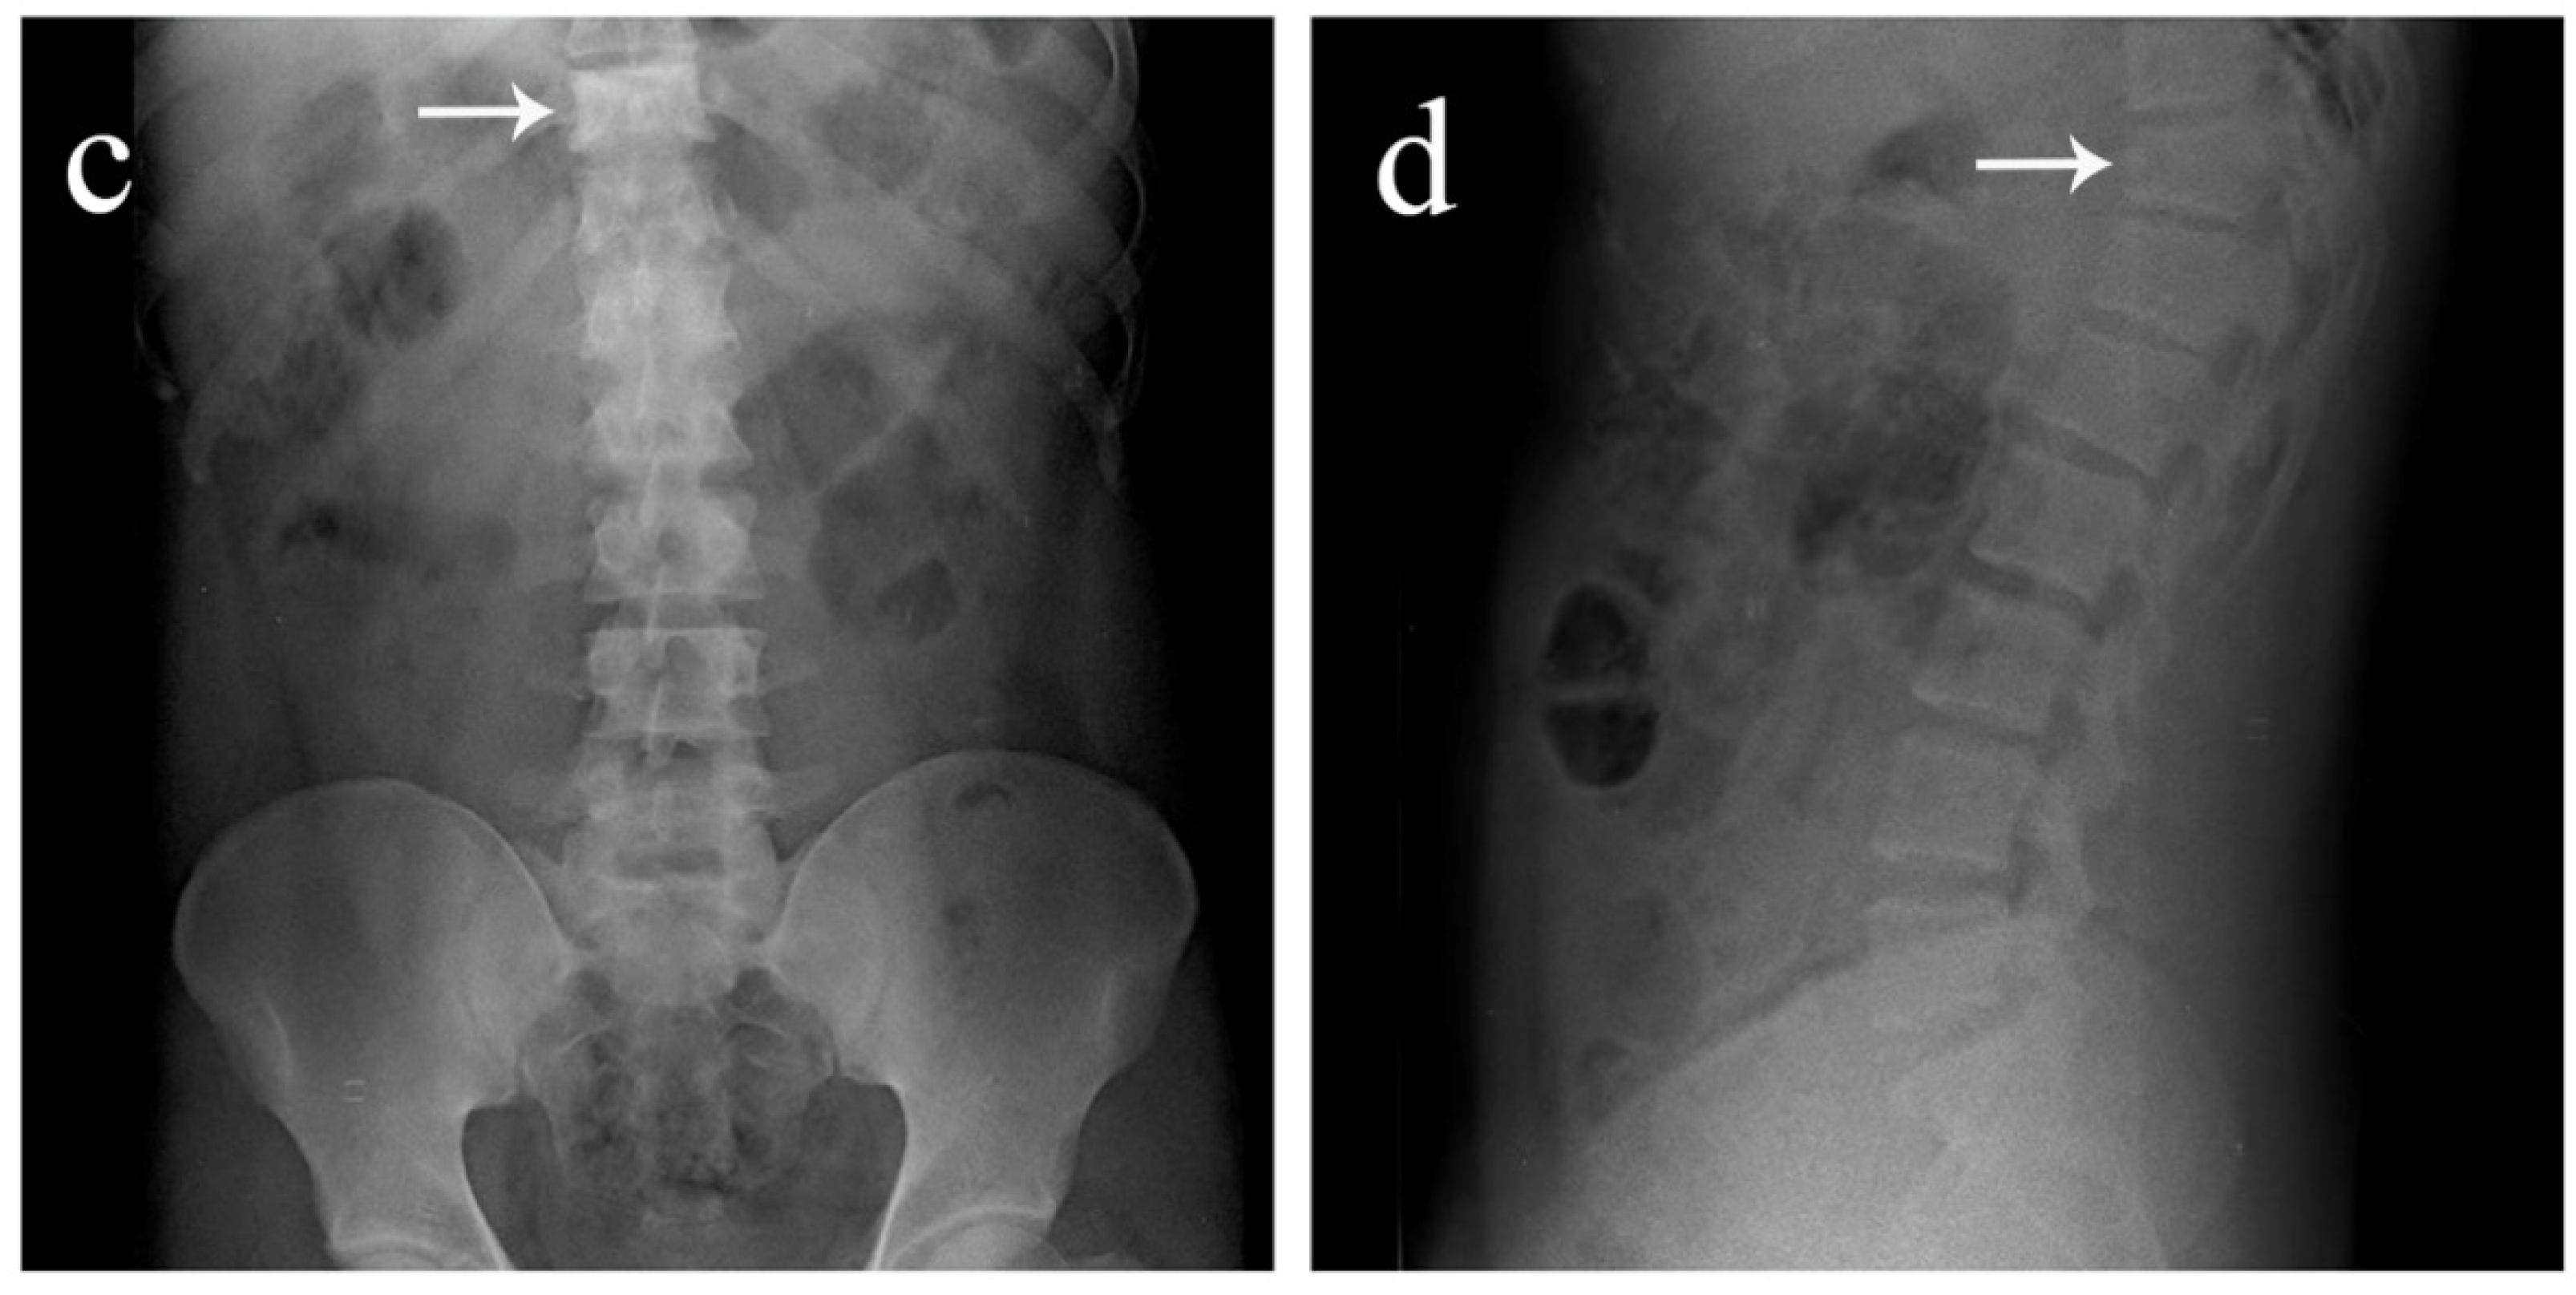

Figure 1. Antero-posterior and lateral view plain radiographs of a 35-year-old male who was brought to the emergency department with multiple abrasions over the trunk and pain in the upper back following a motor vehicle accident. He was conscious and well oriented with stable vitals. Upon examination, midline tenderness was elicited throughout his upper back. His motor power was 5/5 in all four limbs, and there was no sensory deficit. Plain radiographs revealed an obvious anterior wedge compression fracture of the T11 thoracic vertebra. However, since tenderness was elicited throughout the upper thoracic spine and not confined just to the T11 level, more fractures were suspected. On further examination of the anteroposterior view radiograph, it was noticed that the spinous process shadows of the upper thoracic vertebra were either absent or deviated. This brought suspicion of multiple spinous process fractures, which were later confirmed using a computed tomography (CT) scan. (a) Antero-posterior view of the thoracic spine showing absent or deviated spinous process shadows throughout the upper thoracic spine, raising suspicion of spinous process fractures. (b) Lateral view of the thoracic spine showing a compression fracture of T11 vertebrae (arrow). (c) Antero-posterior view of the lumbar spine where the T11 vertebra appears to be sclerotic (arrow). (d) Lateral view of the lumbar spine showing normal lordosis and the T11 compression fracture (arrow).